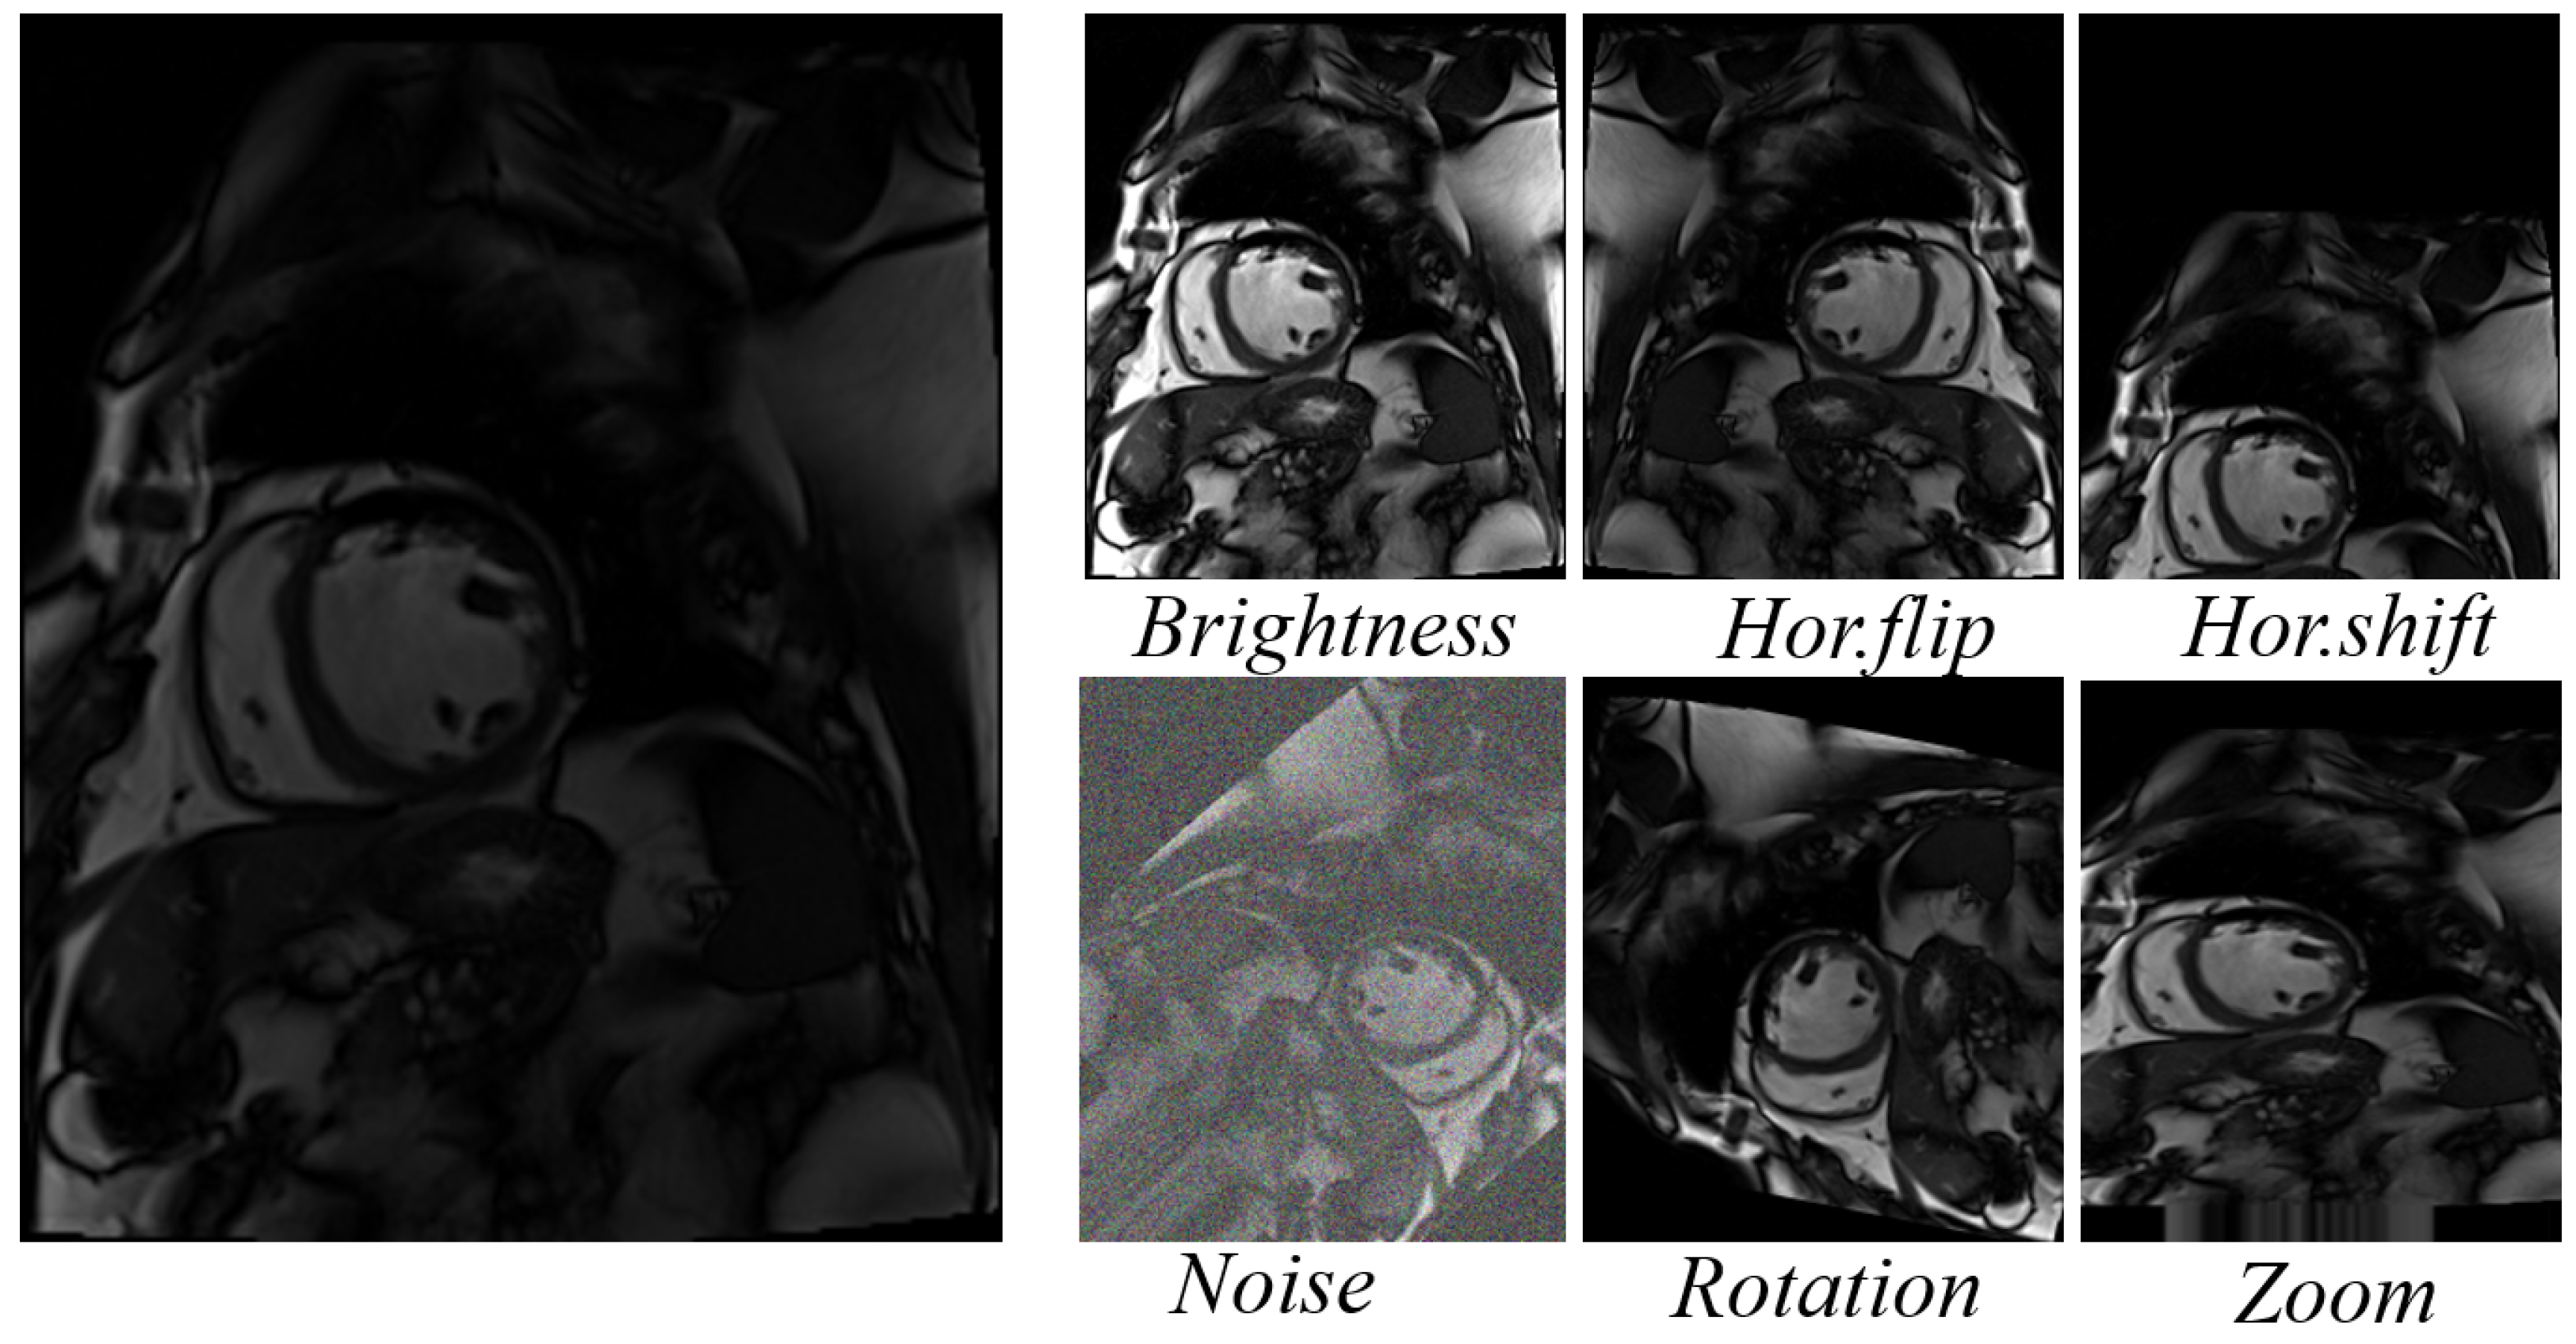

2.3.2. Implementation Details